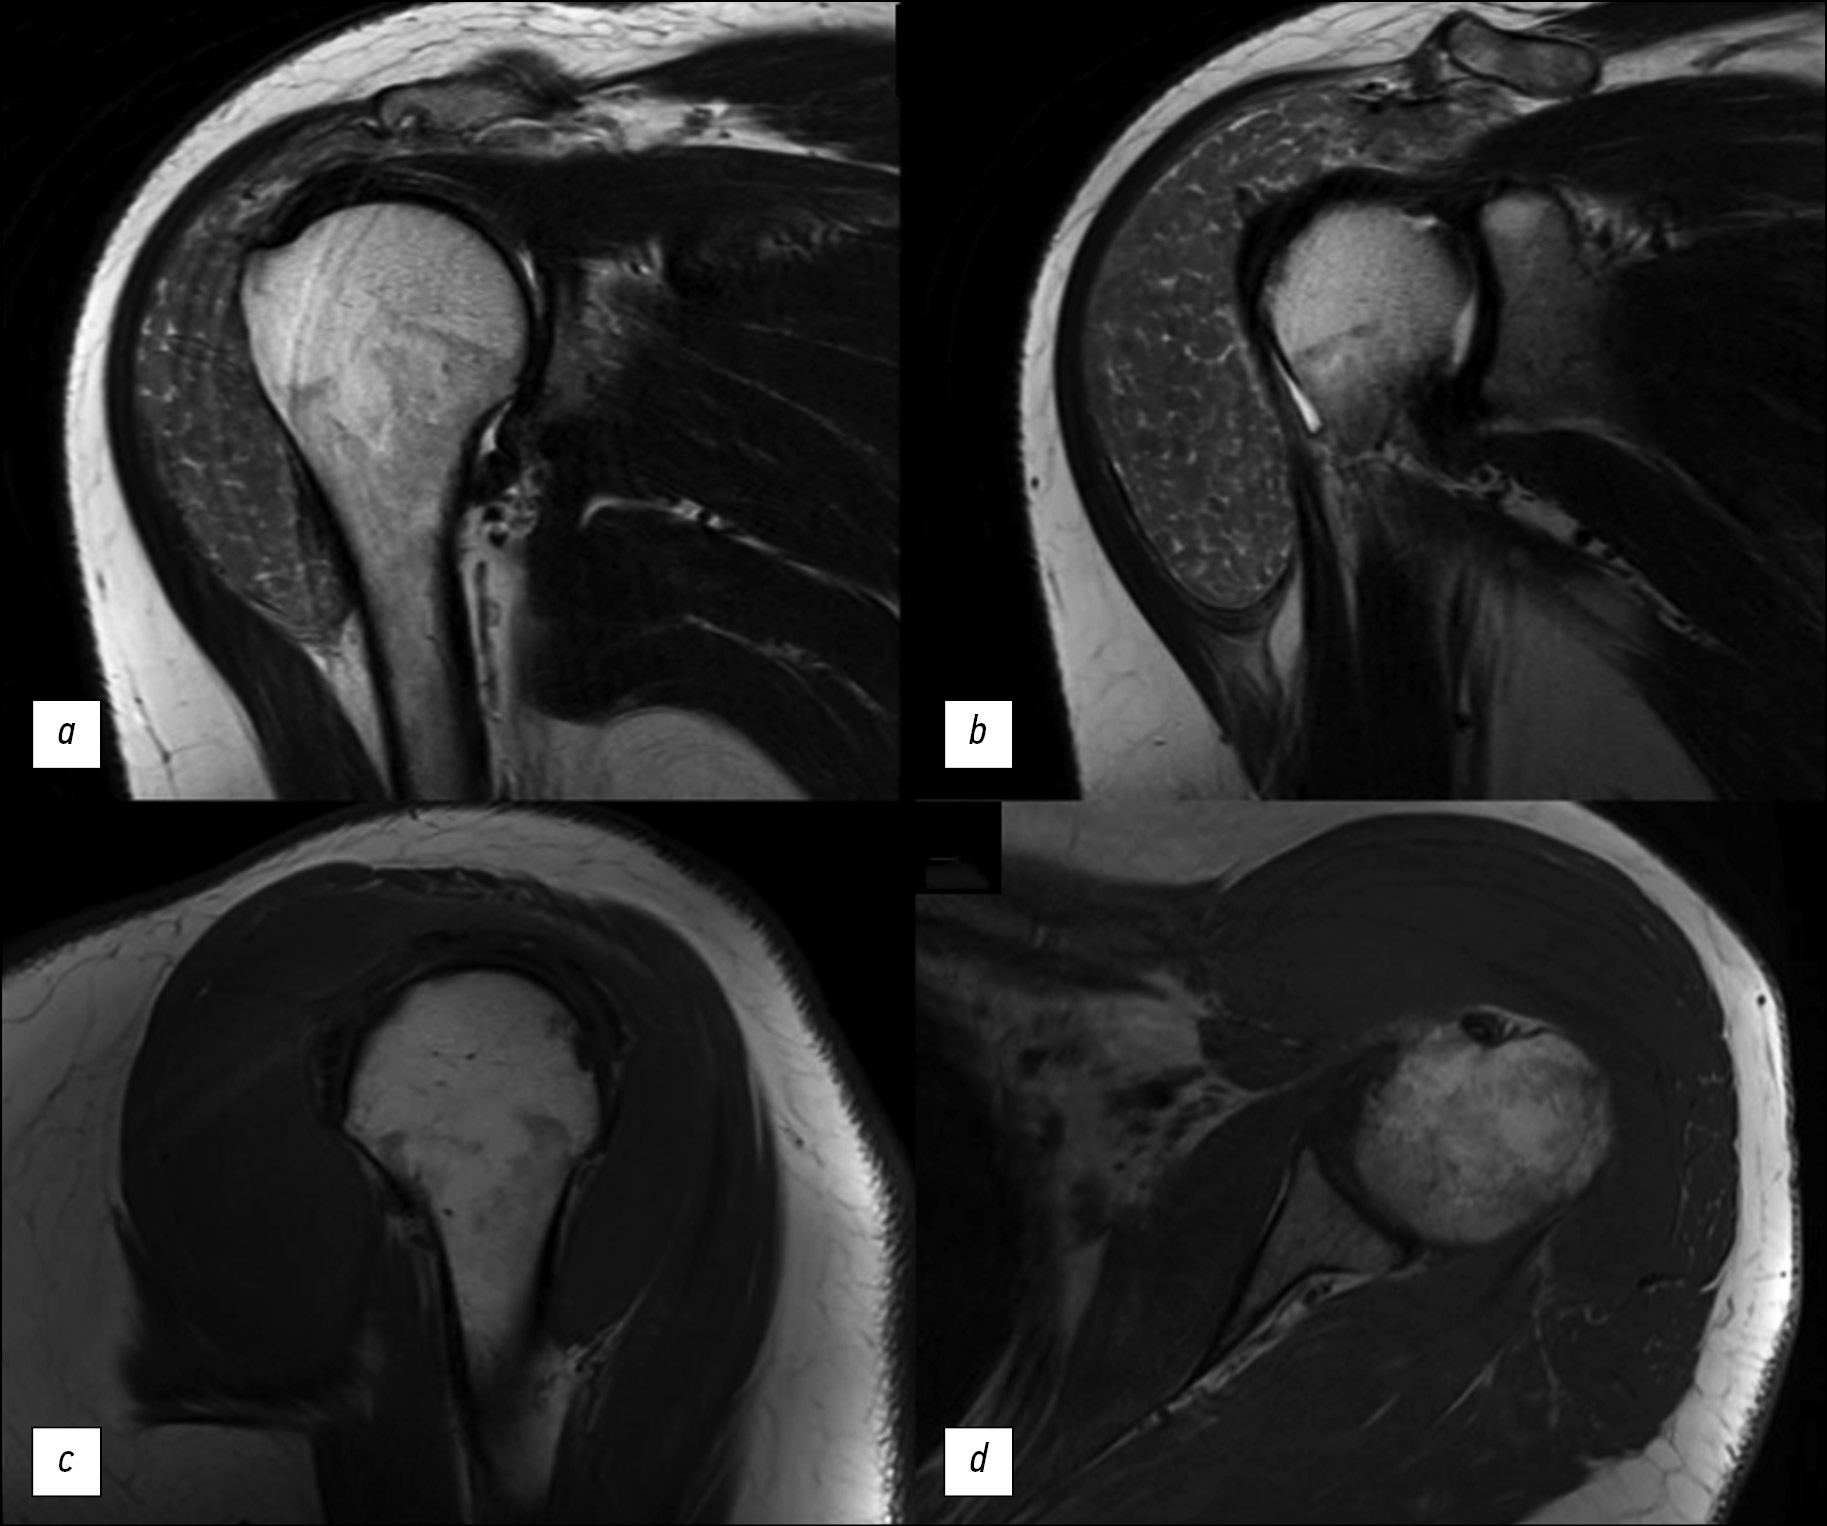

Симптом «рисовых телец» при магнитно-резонансной томографии плечевого сустава у пациентки с ревматоидным артритом

Симптом «рисовых телец» при магнитно-резонансной томографии плечевого сустава у пациентов с ревматоидным артритом — редкая, но специфическая находка, характеризующаяся наличием в синовиальной жидкости сустава, синовиальных сумках или влагалищах множественных мелких округлых структур, схожих друг с другом, похожих на зёрнышки риса. Этиология «рисовых телец» до сих пор окончательно не ясна. Предполагается, что они образуются в результате микроинфарктов синовиальной оболочки у пациентов с ревматоидным артритом или некоторыми другими воспалительными заболеваниями суставов. Клинически наличие «рисовых телец» может вызывать у пациента болевой синдром, однако так происходит не всегда. Среди методов лучевой диагностики ведущей ролью для выявления «рисовых телец» обладает магнитно-резонансная томография.

В данной статье представлено описание клинического случая выявления этого симптома при магнитно-резонансной томографии плечевого сустава у пациентки с длительным анамнезом ревматоидного артрита, обратившейся в связи с безболезненным увеличением в объёме левого плеча. Выполненные исследования (компьютерная томография и магнитно-резонансная томография левого плечевого сустава) позволили обнаружить симптом «рисовых телец» как проявление основного заболевания и определить дальнейшую тактику лечения.